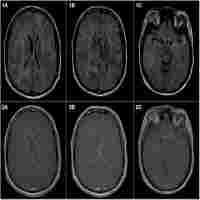

| Abstract | A 30-year-old man with a history of bipolar disease presented with 6 months of cognitive decline, unsteady gait, urinary retention, and bilateral upper extremity tremors. Multiple punctate enhancing lesions were seen on brain MRI (figure). Differential diagnosis included infection (viral, tuberculosis, or cryptococcus), toxic leukoencephalopathy, gliomatosis cerebri, angiocentric lymphoma, and neurosarcoidosis. CT chest scan, CSF studies, HIV testing, hepatitis panel, drug screen, and vasculitis panel were negative. Brain biopsy revealed neurosarcoidosis. The patient responded well to high-dose steroids and IV cyclophosphamide. MRI in neurosarcoidosis often reveals enhancing periventricular white matter lesions, in this case mimicking diffuse gliomatosis cerebri.1,2 |